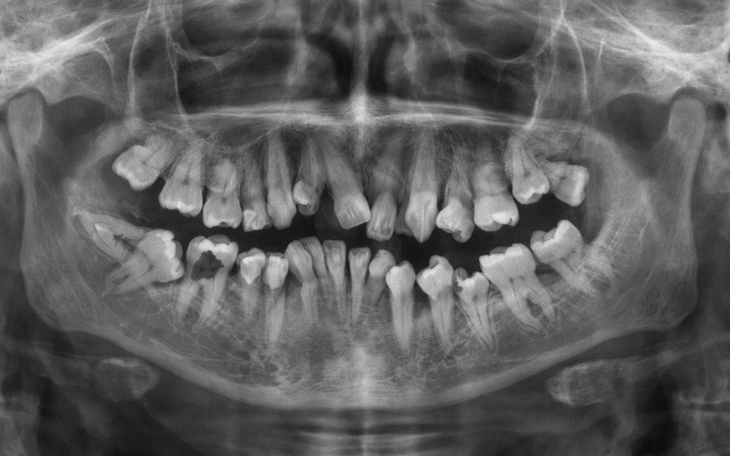

Moje zęby są krzywe, część rośnie w niewłaściwych kierunkach, a niektóre wciąż są zatrzymane w dziąśle i nie wybiły się prawidłowo. Powoduje to silny ból, częste stany zapalne oraz ogromny dyskomfort podczas jedzenia i mówienia. Każdy dzień przypomina mi o tym problemie.

Po konsultacji stomatologicznej dowiedziałem się, że konieczne jest kompleksowe leczenie – chirurgiczne, stomatologiczne oraz ortodontyczne. Niestety koszty takiego leczenia są bardzo wysokie i przekraczają moje możliwości finansowe.